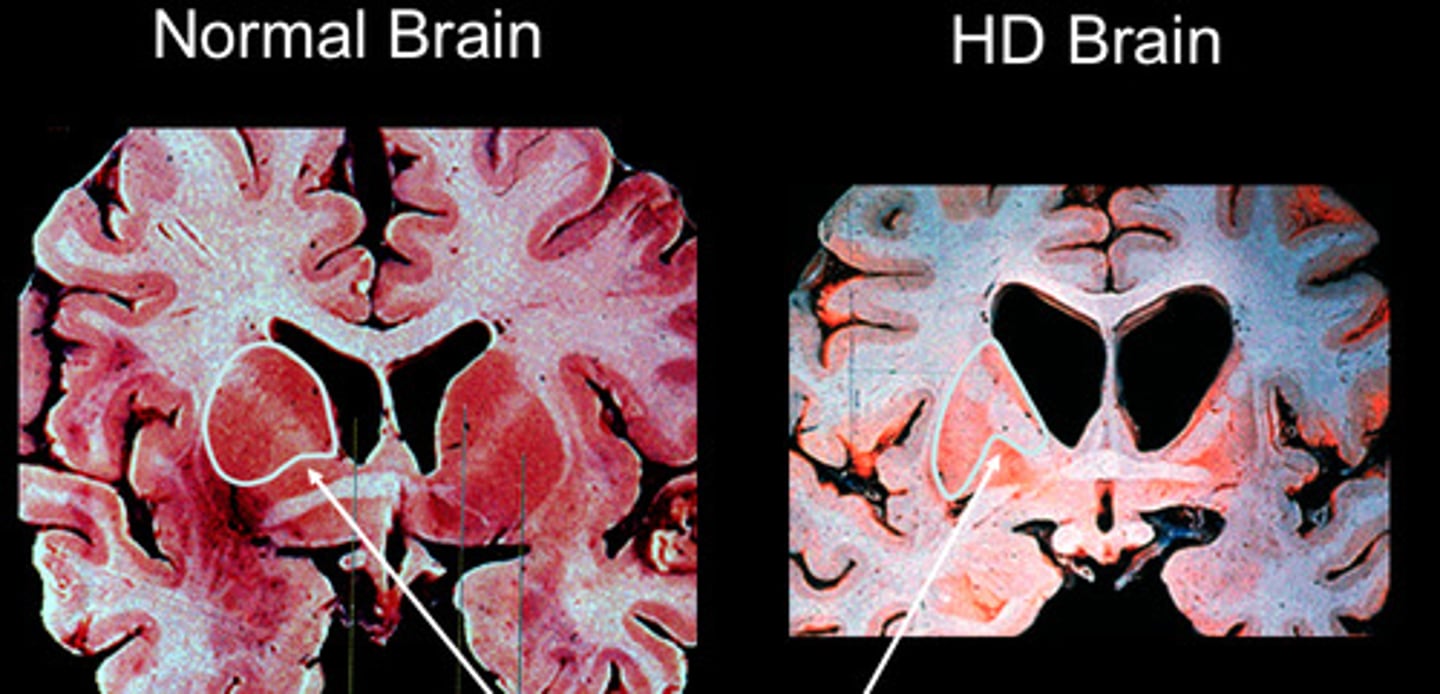

Chorea, dementia, caudate degeneration

Huntington disease (AD, CAG repeat expansion)

Hemiballismus caused by subthalamic nuclei (STN)

Loss of GABAergic neurons